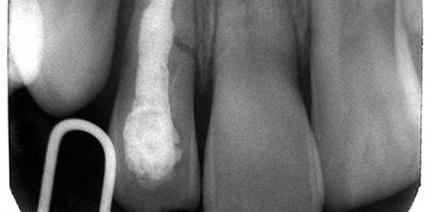

Die Langzeitbehandlung von Wurzelfrakturen

Wurzelfrakturen sind als komplexe Traumata zu betrachten, da sie sowohl die Zahnhartsubstanz als auch die parodontalen und pulpalen Gewebe betreffen. Die Therapie einer Wurzelfraktur richtet sich nach der Lage der Fraktur, nach Art und Ausmaß der Dislokation des koronalen Fragments sowie nach dem Stadium des Wurzelwachstums. weiterlesen